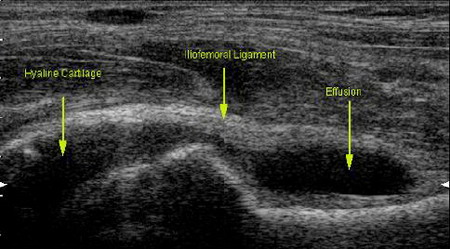

. Tổn thương viêm màng hoạt dịch trên siêu âm

• Siêu âm phát hiện 100% bệnh nhân có viêm MHD.

• Độ dày trung bình MHD viêm: 3,7 ± 0,57mm (từ 3-6mm). Độ dày trung bình MHD của người bình thường: 1,45±0,28mm (từ 0,8-2,2mm).

• Phân bố vị trí viêm MHD trên siêu âm

- Khớp quay-trụ xa: 3,8 ± 0,56 (có 73/76 - 96,1% bệnh nhân có tổn thương)

- Khớp quay-cổ tay: 3,6 ± 0,53 (có 71/76 -93,4% bệnh nhân có tổn thương)

- Khớp cổ-bàn tay: 3,6 ± 0,61) ( có 71/76 - 93,4% bệnh nhân có tổn thương)

(Không có sự khác biệt về độ dày MHD viêm giữa các vị trí khớp (p> 0,05))

• So sánh 12 bệnh nhân được khảo sát cả siêu âm, X quang và cộng hưởng từ. Kết quả cho thấy 100% bệnh nhân phát hiện được tổn thương viêm MHD trên siêu âm được khẳng định trên CHT. Tương tự kết quả trên siêu âm,  không có sự khác biệt giữa các vị trí viêm MHD trên CHT.

1.1. Đặc điểm viêm màng hoạt dịch trên siêu âm

saviem_mhd_resize.jpgViêm MHD là triệu chứng xuất hiện sớm nhất của bệnh VKDT. Siêu âm hoặc cộng hưởng từ dễ dàng phát hiện tổn thương viêm MHD trong khi X quang không phát hiện được. Màng hoạt dịch viêm trong giai đoạn sớm của bệnh phù nề, xung huyết thể hiện trên siêu âm là sự tăng kích thước của MHD so với bình thường (≥ 3mm). Càng ở những giai đoạn sau MHD viêm tái đi tái lại nhiều lần sẽ đẫn đến hiện tượng xơ hóa và do vậy độ dày MHD cũng giảm hơn ở những giai đoạn đầu. Trong nghiên cứu của chúng tôi 100% bệnh nhân có viêm MHD. Bề dày trung bình MHD viêm là 3,7 ± 0,57 mm (từ 3-6 mm); cao hơn 1,4 lần so với nhóm người bình thường: 1,45 ± 0,28 mm (từ 0,8-2,2 mm). Chúng tôi cũng không thấy có sự khác biệt giữa 3 vị trí viêm MHD ở cổ tay. Tỉ lệ viêm MHD dịch ở khớp quay- trụ xa khớp quay- cổ tay, khớp cổ - bàn tay lần lượt là 96% và 93,4%. Bề dày trung bình của MHD viêm ở 3 vị trí lần lượt là 3,8 ± 0,56 mm; 3,6 ± 0,53 mm; 3,6 ± 0,61 mm. Nghiên cứu của Lê Thị Hải Hà về hình ảnh cộng hưởng từ khớp cổ tay trên 42 bệnh nhân VKDT (2006) cũng cho thấy không có sự khác biệt về mức độ viêm MHD ở 3 vị trí khớp [1].